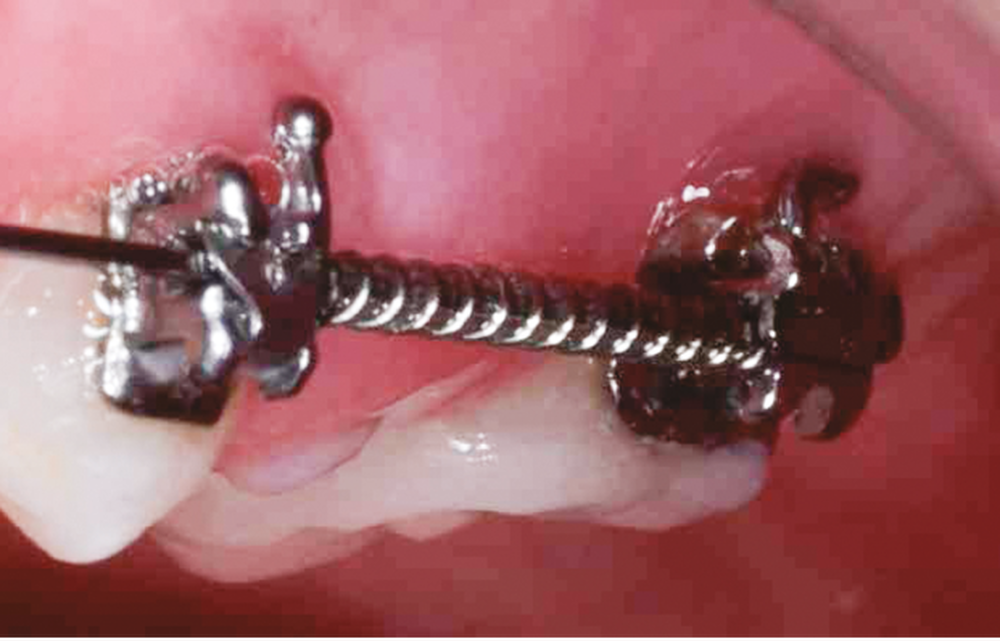

Le protocole de préparation de la dent ainsi que celui concernant l’assemblage de l’overlay céramique (fig. 2 à 7) suivent une séquence clinique habituelle [7, 8], à l’exception de deux étapes. Nous proposons ici, à la suite de l’éviction carieuse, d’intensifier la désinfection par l’utilisation d’O3 (fig. 3). Aussi, il nous paraissait intéressant, une fois la préparation prothétique effectuée, d’infiltrer cet « émail MIH » afin de potentialiser le collage et renforcer ses propriétés mécaniques ; l’infiltration résineuse agirait à l’échelle de l’émail comme le scellement dentinaire immédiat agit à l’échelle de la dentine (fig. 5). Une désinfection optimisée, un bandeau d’émail renforcé et le choix d’une restauration minimalement invasive qu’est l’overlay conduisent à un pronostic plus favorable pour l’avenir de cette dent, d’ailleurs incluse par la suite dans un traitement orthodontique (fig. 8).